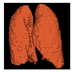

Based on the results of the evaluation metrics for each architecture in Table 5, surprisingly, 3D UNet is better than the other six methods. Compared with the 3D VGGUNet architecture with transfer learning, which achieved the second best result on average, 3D UNet improved by 0.37%, 0.23%, 0.03%, and 0,19% in IoU score, Dice score, accuracy, and F1-score, respectively. Although 3D UNet has the best evaluation of metrics compared to other architectures, 3D UNet has the longest maximum learning iteration process of 1663, in contrast to other architectures, which are modifications of 3D UNet, and which have an average maximum learning iteration of 278. Of the seven models that have been tried, 3D DenseUNet obtained first place as the architecture with the fastest learning time, ±4459 s and ±6539 s without transfer learning and using transfer learning, respectively. The 3D UNet architecture stays in the second last position with a learning process time of ±17,217 s, and for the position of the architecture that has the longest training process, it is the 3D VGGUNet, with transfer learning reaching ±23,200 s. The comparison of loss training and testing on the 3D UNet learning process for the lung segmentation is shown in Figure 4. Furthermore, in Table 6, the comparison of ground truth and the prediction results of the 3D UNet model in 2D (slice) and 3D projections for this binary-class segmentation case can be seen.

Table 6. Comparison between ground truth and prediction results of lung segmentation with 3D UNet architecture.

Original CT-ScanGround TruthPrediction

3D ProjectionHealthcare 11 00213 i024Healthcare 11 00213 i025Healthcare 11 00213 i026

Slice (2D)Healthcare 11 00213 i027Healthcare 11 00213 i028Healthcare 11 00213 i029